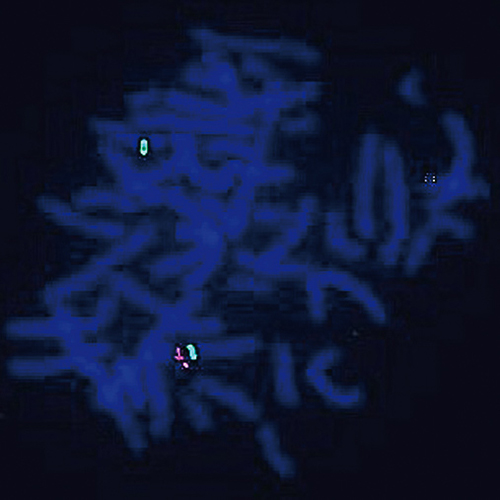

Hybridization of ALK break probe to a lung adenocarcinoma tissue section showing positive translocation signal (1RG1R1G).

Translocations of the ALK (anaplastic lymphoma kinase) gene at 2p23 have originally been associated with anaplastic lymphomas, B-cell lymphomas, neuroblastomas and myofibroblastic tumors. At least 21 translocation partners have been described, however 80% of the translocations involves the NPM1 gene (5q35). ALK rearrangements have been described in non-small cell lung cancer (NSCLC) cases. The ALK (2p23) Break probe is optimized to detect translocations involving the ALK gene region at 2p23.